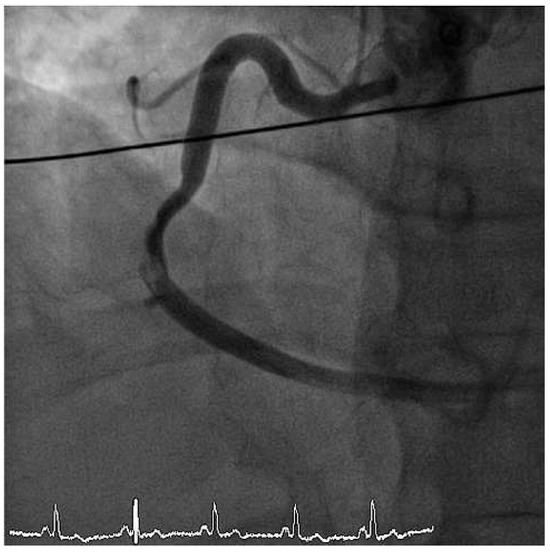

We report the case of a 47-year old man who presented with severe cardiogenic shock and signs of ST-elevation myocardial infarction. Urgent coronary angiography showed thrombotic occlusion of the mid left anterior descending artery (LAD) and the circumflex artery, as well as a [...] Read more.

We report the case of a 47-year old man who presented with severe cardiogenic shock and signs of ST-elevation myocardial infarction. Urgent coronary angiography showed thrombotic occlusion of the mid left anterior descending artery (LAD) and the circumflex artery, as well as a subtotal thrombotic occlusion of the right coronary artery without signs of relevant atherosclerotic coronary disease. The patient was treated with thrombus aspiration in all coronary vessels and PTCA of the LAD with good result. Despite thorough investigation of major nonatherosclerotic causes of myocardial infarction, which are further discussed in our case report, the case remains unsolved. Until today the patient is free of symptoms under long-term dual antiplatelet-inhibitor therapy. Full article